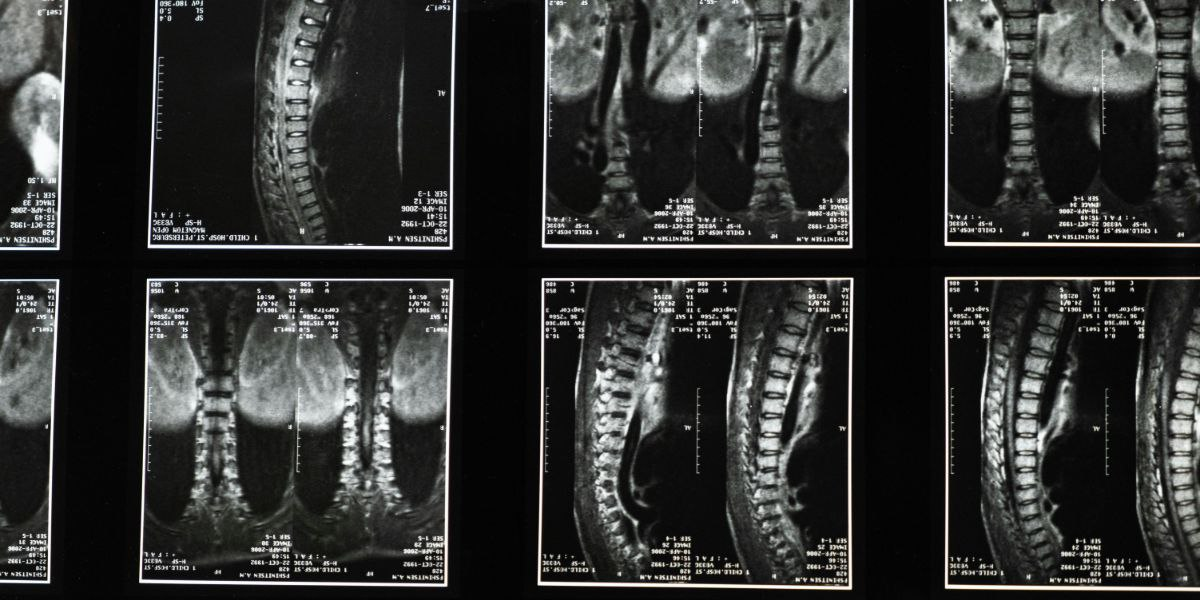

Предыдущие исследования сообщали о безопасности и переносимости имплантации нейронных стволовых клеток пациентам с травмой спинного мозга. В текущем исследовании первой фазы ученые оценили лечение четырех пациентов с хроническими травмами спинного мозга, средний возраст которых составлял 30 лет. Наблюдения проводились каждые 6 месяцев в течение пяти лет и включали опросники по боли, оценку качества жизни, оценку двигательного контроля мозга и МРТ-визуализацию.